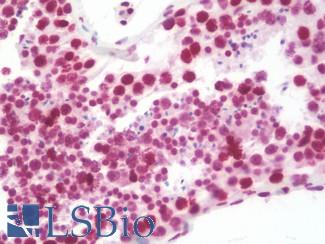

Estrogen Receptor / ESR1

Anti-ER Alpha / Estrogen Receptor antibody IHC staining of human breast. Immunohistochemistry of formalin-fixed, paraffin-embedded tissue after heat-induced antigen retrieval. Antibody LS-B10527 dilution 1:100.